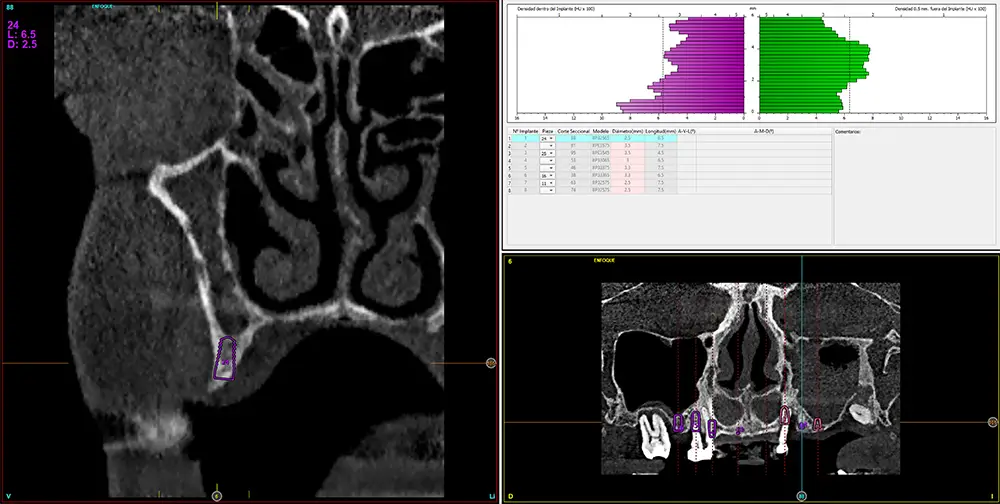

Para realizar una planificación precisa del caso y determinar el volumen óseo residual antes de la cirugía implantológica, se realiza un estudio mediante tomografía de haz cónico (cone-beam) y se visualiza mediante un software específico (BTI-Scan IV). Esta exploración permite medir con exactitud la altura y anchura de la cresta ósea, así como evaluar la densidad de las zonas en las que se prevé colocar los implantes, facilitando así una planificación quirúrgica fiable y ajustada a las necesidades anatómicas del paciente44–47. En las imágenes del cone-beam de control, observamos en el segundo cuadrante una atrofia vertical extrema, con zonas de menos de 4 mm de altura, donde se planifican implantes de 4,5 mm de longitud que serán colocados mediante el procedimiento de elevación transcrestal con fresa de corte frontal y con hueso autólogo obtenido del fresado embebido en PRGF-Endoret como material de injerto. Esta técnica, descrita por nuestro grupo de estudio, nos permite realizar un abordaje seguro del seno maxilar con una escasa invasividad (figs. 8-10)9,25,29,36.

Figs. 9-10. Medida de la zona con mayor atrofia del segundo cuadrante menor a 4 mm de altura y planificación del implante de 4,5 mm de longitud que será colocado mediante el procedimiento de elevación transcrestal anteriormente descrito.